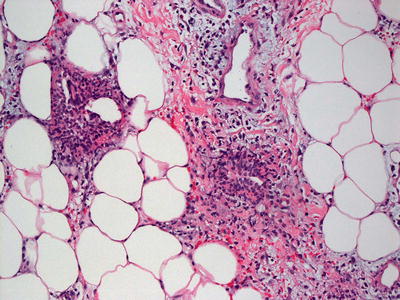

Erythema nodosum is a septal panniculitis [1]. Early lesions demonstrate septal edema and a mixed inflammatory infiltrate of neutrophils, lymphocytes, eosinophils, and occasional giant cells (Fig. 9.1). As the lesions develop, neutrophils diminish in number with increased number of histiocytes, including multinucleated giant cells (Figs. 9.2 and 9.3). Small granulomatous foci are present in some cases. The septa become thickened and fibrotic, and septal edema is less apparent. The inflammatory infiltrate may extend into the periphery of the fatty lobules, although fat necrosis is not seen. The blood vessels are not inflamed. The overlying epidermis and dermis are usually relatively unremarkable.

Fig. 9.2

Abundant lymphocytes, scattered eosinophils and histiocytes, including multinucleated giant cells, are seen within the fibrous septa in erythema nodosum